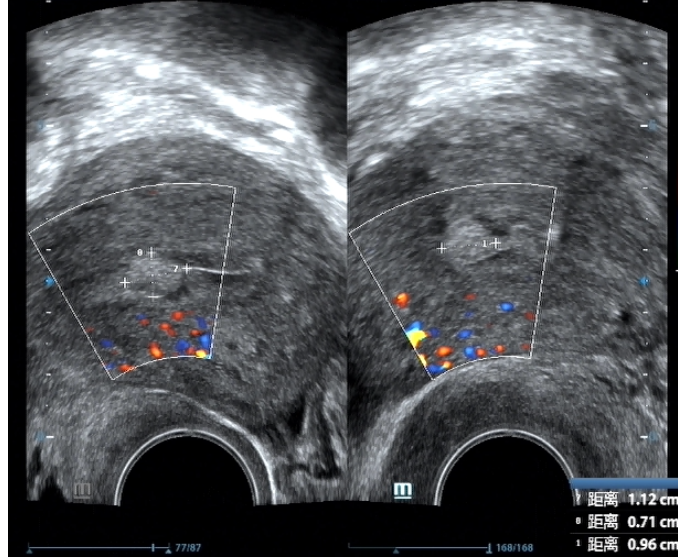

子宫内膜息肉是子宫内膜局部过度增生形成的肿物,它们可以在超声检查中表现为局部回声增强或不均匀。息肉的大小和数量不一,可单发或多发,也可能引起异常的阴道出血、不孕等问题。

子宫内膜息肉在围绝经期和绝经后女性中较为常见,加拿大妇产科医师协会 2024 年指南指出,子宫内膜息肉的恶变风险在一般人群中约为 0.5%-5.4%,但是在以下这些人群中,恶变风险会增加。

子宫内膜息肉形成原因较为复杂,涉及激素水平失衡、慢性炎症刺激、血管生成异常、基因和遗传因素、药物影响以及生活方式等多种因素。在高危人群中,我们应加强监测和管理。

超声检查中,增生的子宫内膜可能表现为回声不均匀或局部增厚。子宫内膜增生的高发年龄段以围绝经期以及绝经期女性为主,处在该年龄段的女性以及有高危因素的女性朋友,尤其当合并异常的阴道出血时,我们应该警惕该疾病可能。

而当绝经后女性的单层子宫内膜厚度超过4mm时,更需警惕子宫内膜癌的可能,尤其是伴有肥胖、未对抗的雌激素使用、多囊卵巢综合征、2型糖尿病等高危因素的患者。超声检查中,子宫内膜癌可能表现为回声不均匀、形态不规则或局部明显增厚。